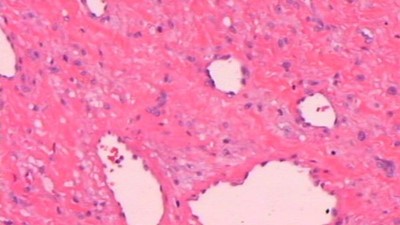

- nádor(y) mozku

- nádor(y) srdce

- nádor(y) plic

- nádor(y) ledvin